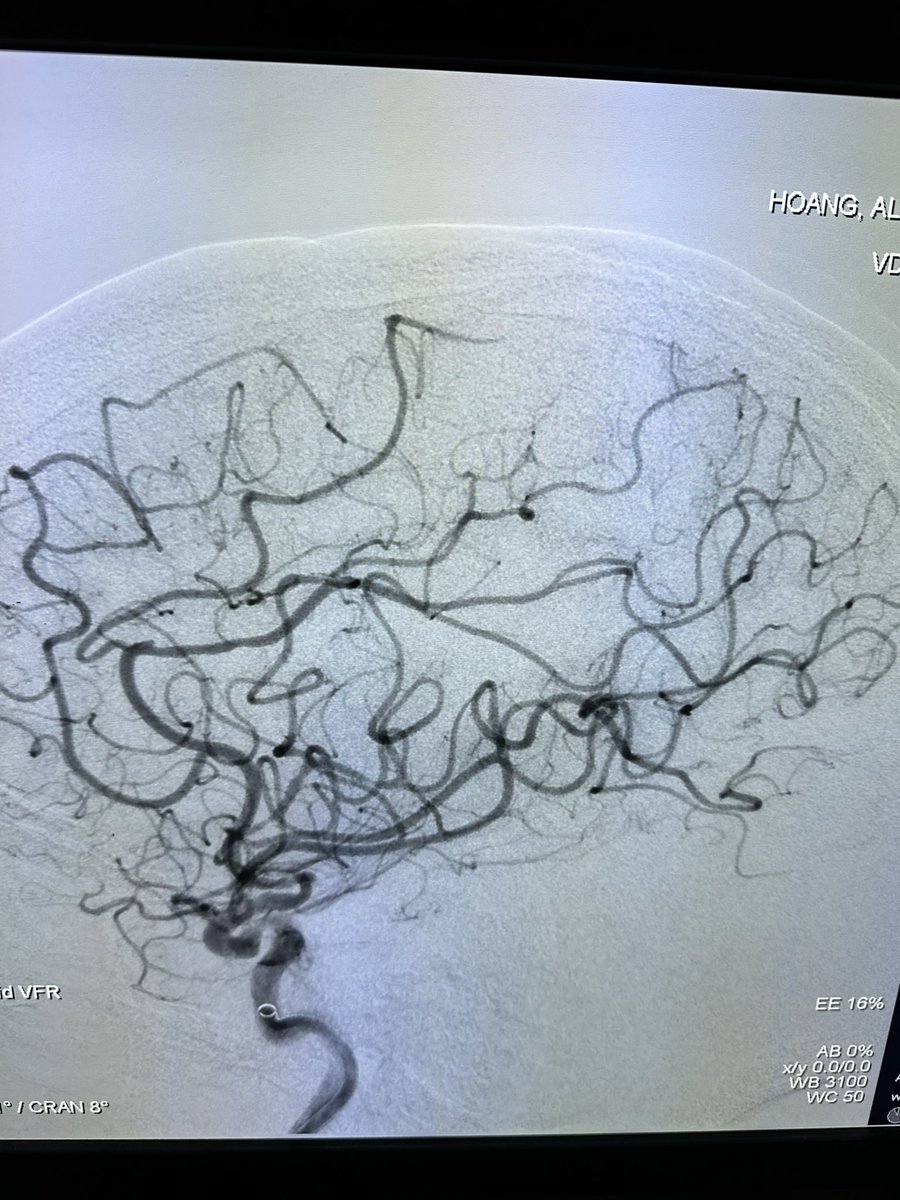

Great talk by @ShahidNimjee about VWF inhibiting aptamer for thrombolysis. This research has come along way and will improve stroke therapy in the future. It may be the beginning of the end of stroke mechanical thrombectomy. #SNIS2023 @OSUWexMed @NeurosurgeryOSU